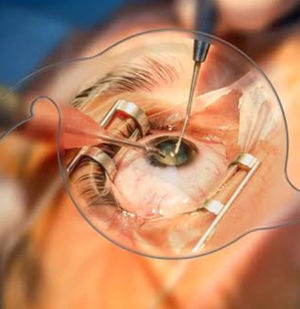

Vitreoretinal surgery is a highly specialized field of ophthalmology dealing with diseases of the retina and vitreous — the innermost structures of the eye responsible for vision. Dr. Tekchandani performs advanced procedures such as pars plana vitrectomy, scleral buckling, and macular hole surgery to restore and preserve sight.

Yes. In addition to advanced retinal procedures, Dr. Uday Tekchandani is an expert in performing micro-incision cataract surgeries using premium intraocular lenses. These surgeries are performed with the “No Injection, No Patch, No Stitch” technique — ensuring faster recovery, minimal discomfort, and crystal-clear vision restoration.